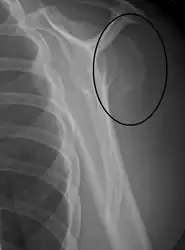

A fracture of the greater tuberosity as seen on AP X ray

A fracture of the greater tuberosity of the humerus